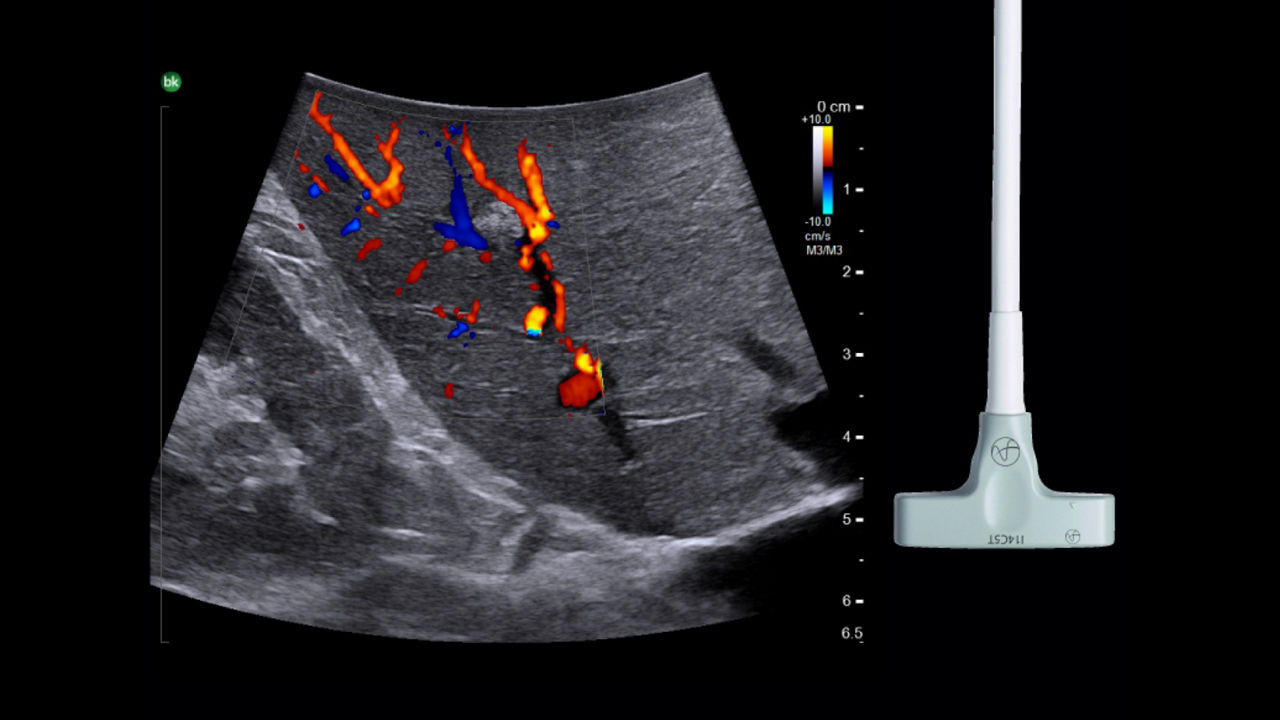

Cholecystectomy ultrasound

Active imaging with real-time intraoperative ultrasound supports fast imaging of the biliary system and is non-radiating, helping you reduce radiation hazards to your patients and staff.

Imaging to guide cholecystectomies

Discover the clinical benefits of active imaging with intraoperative ultrasound for laparoscopic cholecystectomy procedures. Using bkActiv and the Advanced Laparoscopic Transducer, surgeons can visualize anatomy and monitor progress as many times as needed during the procedure.

iUS is beneficial for cholecystectomies due to its safety, quick and repeatable imaging capabilities and ability to detect choledocholithiasis and enable visualization of biliary tract anatomy.

• iUS has minimal safety risks as it is non-irradiating and does not required cannulation. ¹⁻³

• iUS can be used dynamically throughout dissection adding minimal time to a cholecystectomy procedure. iUS can also repeated, helping to assess common bile duct integrity at the end of the procedure.¹⁻⁵

• iUS helps differentiate between sludge, stone, polyps, cysts, and tumors when determining if there is a presence of gallstones in the common bile duct.⁵,⁶

• iUS uses color flow doppler to help differentiate between vessels and ducts and is overall effective at imaging difficult cases such as inflammation or fibrosis .¹,⁴⁻⁶